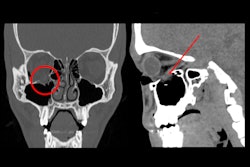

The images on the left side of the white vertical bar show a bilateral, simple, and nondisplaced nasal fracture. The nasofrontal suture (orange arrows), nasal septum (green arrow), and anterior nasal spine (yellow circles) remain intact, while the fracture line crosses the left nasomaxillary suture (red arrows). On the other hand, the image on the right contains a bilateral, comminuted, and displaced nasoseptal fracture (red circle), in which the nasal septum is also involved (red arrow).